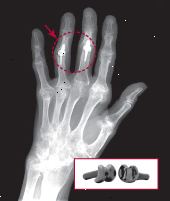

X-ray ukazuje ruku s 57-rok-stará žena s osteoartrózou. Druhá spoje prostřední prst a prsteník získaly umělé proximální interfalangeální klouby vyrobené z pyrocarbon (vložené foto). X-ray se svolením, Barry P. Simmons, MD, vložka Foto s laskavým svolením Ascension Orthotics |

Stejně jako u MCP kloubů, chirurgové používají i silikon a pyrocarbon nahradit proximální interfalangeální kloub, druhý nebo prostřední kloub prstu (viz x-ray). Tyto spoje jsou vhodnými kandidáty pro náhradu, protože kloubní nepohyblivost, a to zejména z kruhu a malé prsty, může být obtížné pochopit objekty. Studie z roku 2007 v The Journal of chirurgie ruky zjištěno, že dva typy implantátů provádí stejně dobře na zmírnění bolesti a zlepšení rozsahu pohybu. Obnova z těchto operací trvá asi tak dlouho, jak zotavuje z koncového kloubu výměnu.